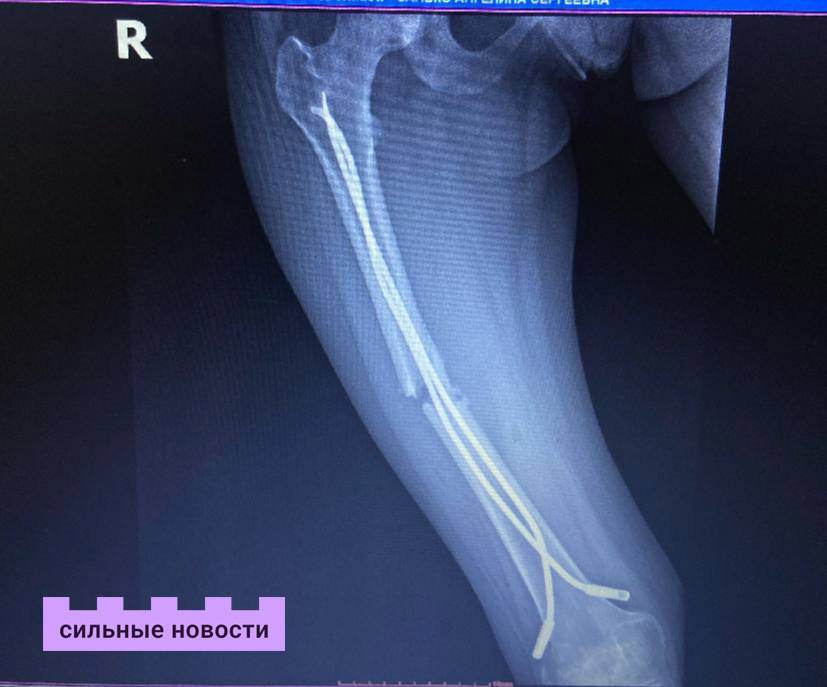

Пару месяцев назад «Сильные Новости» рассказали историю 18-летней гомельчанки, которая попала в ДТП на мотоцикле. Напомним, что авария произошла 15 августа 2024 года. Тогда Ангелина попала в больницу с переломом бедра с сильным смещением. Несколько дней она пролежала на вытяжке, а потом ей сделали операцию, на которой вставили металлоконструкцию, и надели гипс. В нем девушка прожила полгода, выслушивала неутешительные прогнозы врачей и проходила тяжелую реабилитацию.

Врачи направляли Ангелину то к одному специалисту, то к другому, а они ничего внятного не говорили. На снимках сама девушка без медицинского образования видела смещение и несросшийся спустя 11 месяцев перелом. Тогда на помощь пришла ее сестра. Вместе с мужем они нашли хорошего травматолога, который осмотрел девушку и сказал, что нужна повторная операция.

Ангелина согласилась на третий вариант: интрамедуллярный гвоздь с винтами. Он не восстановит полностью длину ноги, но с ним относительно быстро можно начинать ходить.